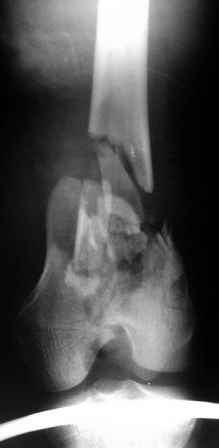

Рентгенограммы.